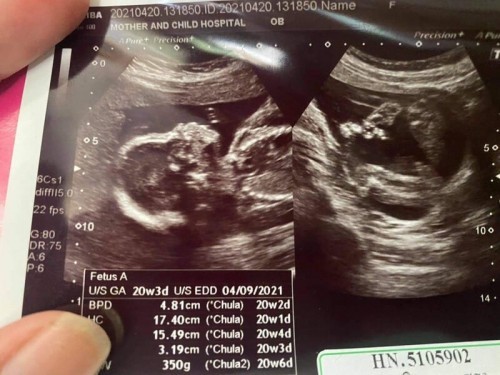

ลองทายเล่นๆดูค่ะ แม่ๆคิดว่าเพศอะไรค่ะ🤰

อยากทราบว่าภาพของคุณแม่ท่านไหนมีบอกมั้ยค่ะว่า เพศอะไรค่ะ👶💙

ชายค่ะโด่ชัดเลย

5555 มีจุ๊ดจู๋ค่ะ

เพศชายค่ะ

ผช. ค่ะ

ชายค่ะ